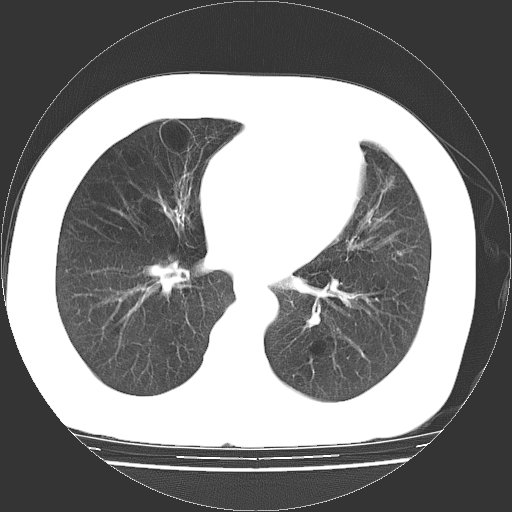

标题: CT13141:女,70岁,咳嗽、胸闷半个月。 [打印本页]

标题: CT13141:女,70岁,咳嗽、胸闷半个月。

女,70岁,咳嗽、胸闷半个月。纵隔窗未见异常,未上传。

双肺肺气肿并多发肺大泡

慢性支气管炎合并小叶中心性肺气肿,多发性肺大泡

慢性支气管炎并小叶中心性肺气肿及间隔旁肺气肿.(多与吸烟有关)。